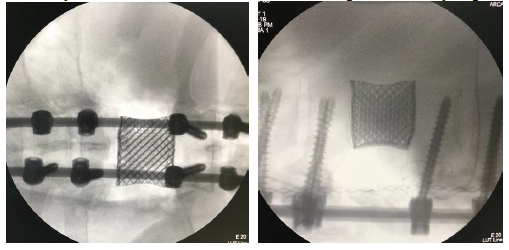

В ножки дуг выше- и нижерасположенных позвонков под контролем ЭОП вводятся винты, устанавливаются продольные балки. Производится компрессия за выше- и нижележащие винты, что позволяет произвести коррекцию кифотической деформации. Производится закрепление конструкции гайками и поперечным коннектором. Всем пациентам проводился рентген-контроль во время операции, после установки импланта и задней транспедикулярной фиксации (рисунок 6).

Рисунок 6. Интраоперационные рентген-снимки в прямой и боковой проекциях пациента после тотальной блок резекции Т9 позвонка с последующей установкой индивидуально 3Д импланта тела позвонка.